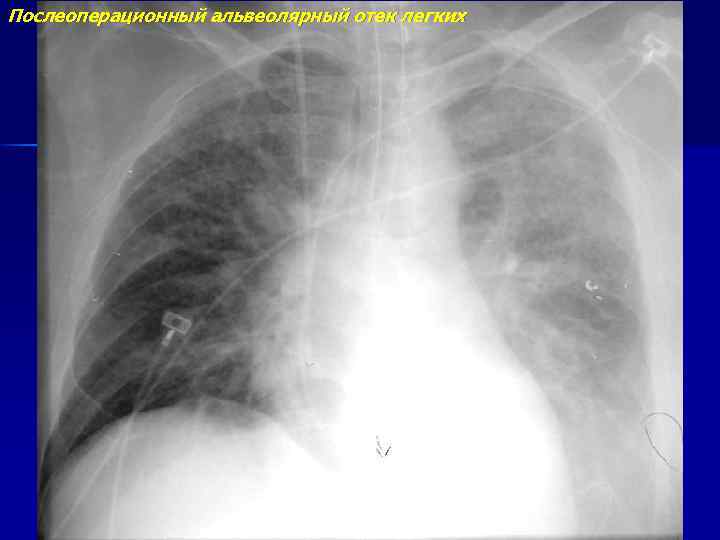

Послеоперационный альвеолярный отек легких